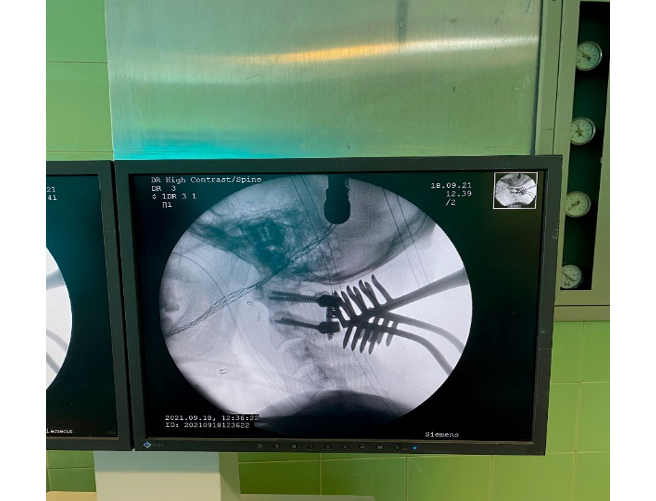

Under general anesthesia, the patient was placed in the supine position. Under fluoroscopy guide and C-ARM imaging monitoring, several times of closed reductions were attempted through gradual manual cranial traction from flexion to extension (Figure-2). To sum up the surgery process; we can say that three phases were done, first of all, the flexion of the head and neck with traction was done, then neutral position applied when the odontoid process was near the posterior wall of the anterior C1 arch. During the process, the odontoid process was locked in the inferior of the anterior C1 arch. Therefore, in the 3rd phase, we decided to push back the odontoid process by using an impactor (Figure-3) through the retro pharynx. The maneuver was successful, and the odontoid was placed in its position. All phases were done under neuromonitoring. Then, He was positioned from supine to prone to fix the C1 and C2 vertebrae. We exposed the axis and atlas surgically via a posterior approach. The attempts to relocate the normal axis-atlas alignment to fuse the facet joints failed. The lateral mass screw was applied for C1, and pedicular 24*8 mm in the right part of C2 and 26*8 mm in the left one was used. The fusion was applied to reduce the ligament injuries (Figure-4 and 5).

Figure 2. the patient under general anesthesia for an external reduction maneuver

Figure 4. intraoperative fluoroscopic images